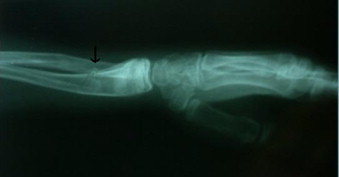

Juvenile osteoporosis is osteoporosis in children and adolescents. Osteoporosis is rare in children and adolescents. When it occurs, it is usually secondary to some other condition,[1] e.g. osteogenesis imperfecta, rickets, eating disorders or arthritis. In some cases, there is no known cause and it is called idiopathic juvenile osteoporosis. Idiopathic juvenile osteoporosis usually goes away spontaneously.[2]

Also, child abuse should be suspected in recurring cases of bone fracture.